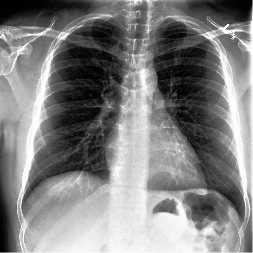

Disease-aware image editing by means of generative adversarial networks (GANs) constitutes a promising avenue for advancing the use of AI in the healthcare sector. Here, we present a proof of concept of this idea. While GAN-based techniques have been successful in generating and manipulating natural images, their application to the medical domain, however, is still in its infancy. Working with the CheXpert data set, we show that StyleGAN can be trained to generate realistic chest X-rays. Inspired by the Cyclic Reverse Generator (CRG) framework, we train an encoder that allows for faithfully inverting the generator on synthetic X-rays and provides organ-level reconstructions of real ones. Employing a guided manipulation of latent codes, we confer the medical condition of cardiomegaly (increased heart size) onto real X-rays from healthy patients. This work was presented in the Medical Imaging meets Neurips Workshop 2020, which was held as part of the 34th Conference on Neural Information Processing Systems (NeurIPS 2020) in Vancouver, Canada

翻译:通过基因对抗网络(GANs)对疾病感官图像进行编辑,通过基因对抗网络(GANs)是推动在保健部门使用AI的有希望的途径。这里,我们展示了这一理念的概念。GAN型技术成功地生成和操纵了自然图像,但其应用于医疗领域的应用仍处于初级阶段。与CheXpert数据集合作,我们显示StyGAN可以接受培训,以产生现实的胸腔X光片。在Cyclic逆向生成器(CRG)框架的启发下,我们培训了一种编码,使该编码能够忠实地在合成X光上翻转生成器,并提供对真实代码进行器官层面的重建。我们利用了对潜在代码的引导操纵,将心型(心脏尺寸增加)的健康状况授予健康病人的真正的X射线。这项工作在作为加拿大温哥华第34次神经信息处理系统会议(NeurIPS 2020)的一部分举行的医学成像会议2020年Neurips讲习班上作了介绍。